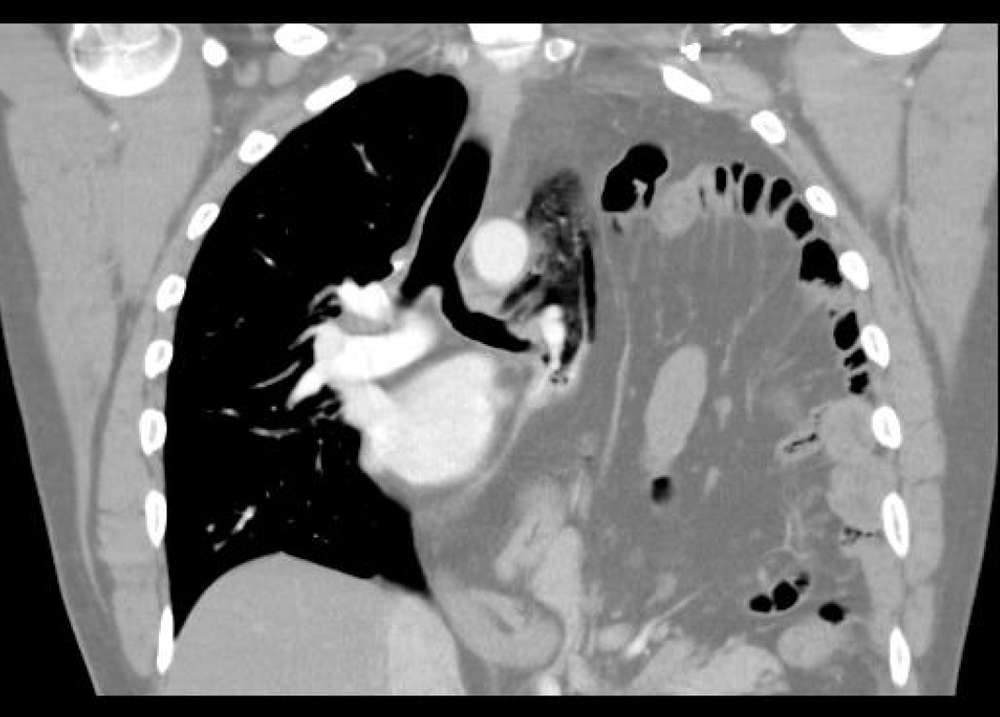

Chronic haematothorax was suspected but multi-detector computer tomography (MDCT) of the thorax confirmed a large left sided diaphragmatic defect with herniation of abdominal contents.

Elective repair was scheduled but the patient presented with acute abdominal pain and type 1 respiratory failure (Pa02 of 7.1kPa with Fi02 of of 60%). Gastric volvulus was diagnosed clinically and decompressed with nasogastric tube insertion. Definitive surgical repair occurred several days later.